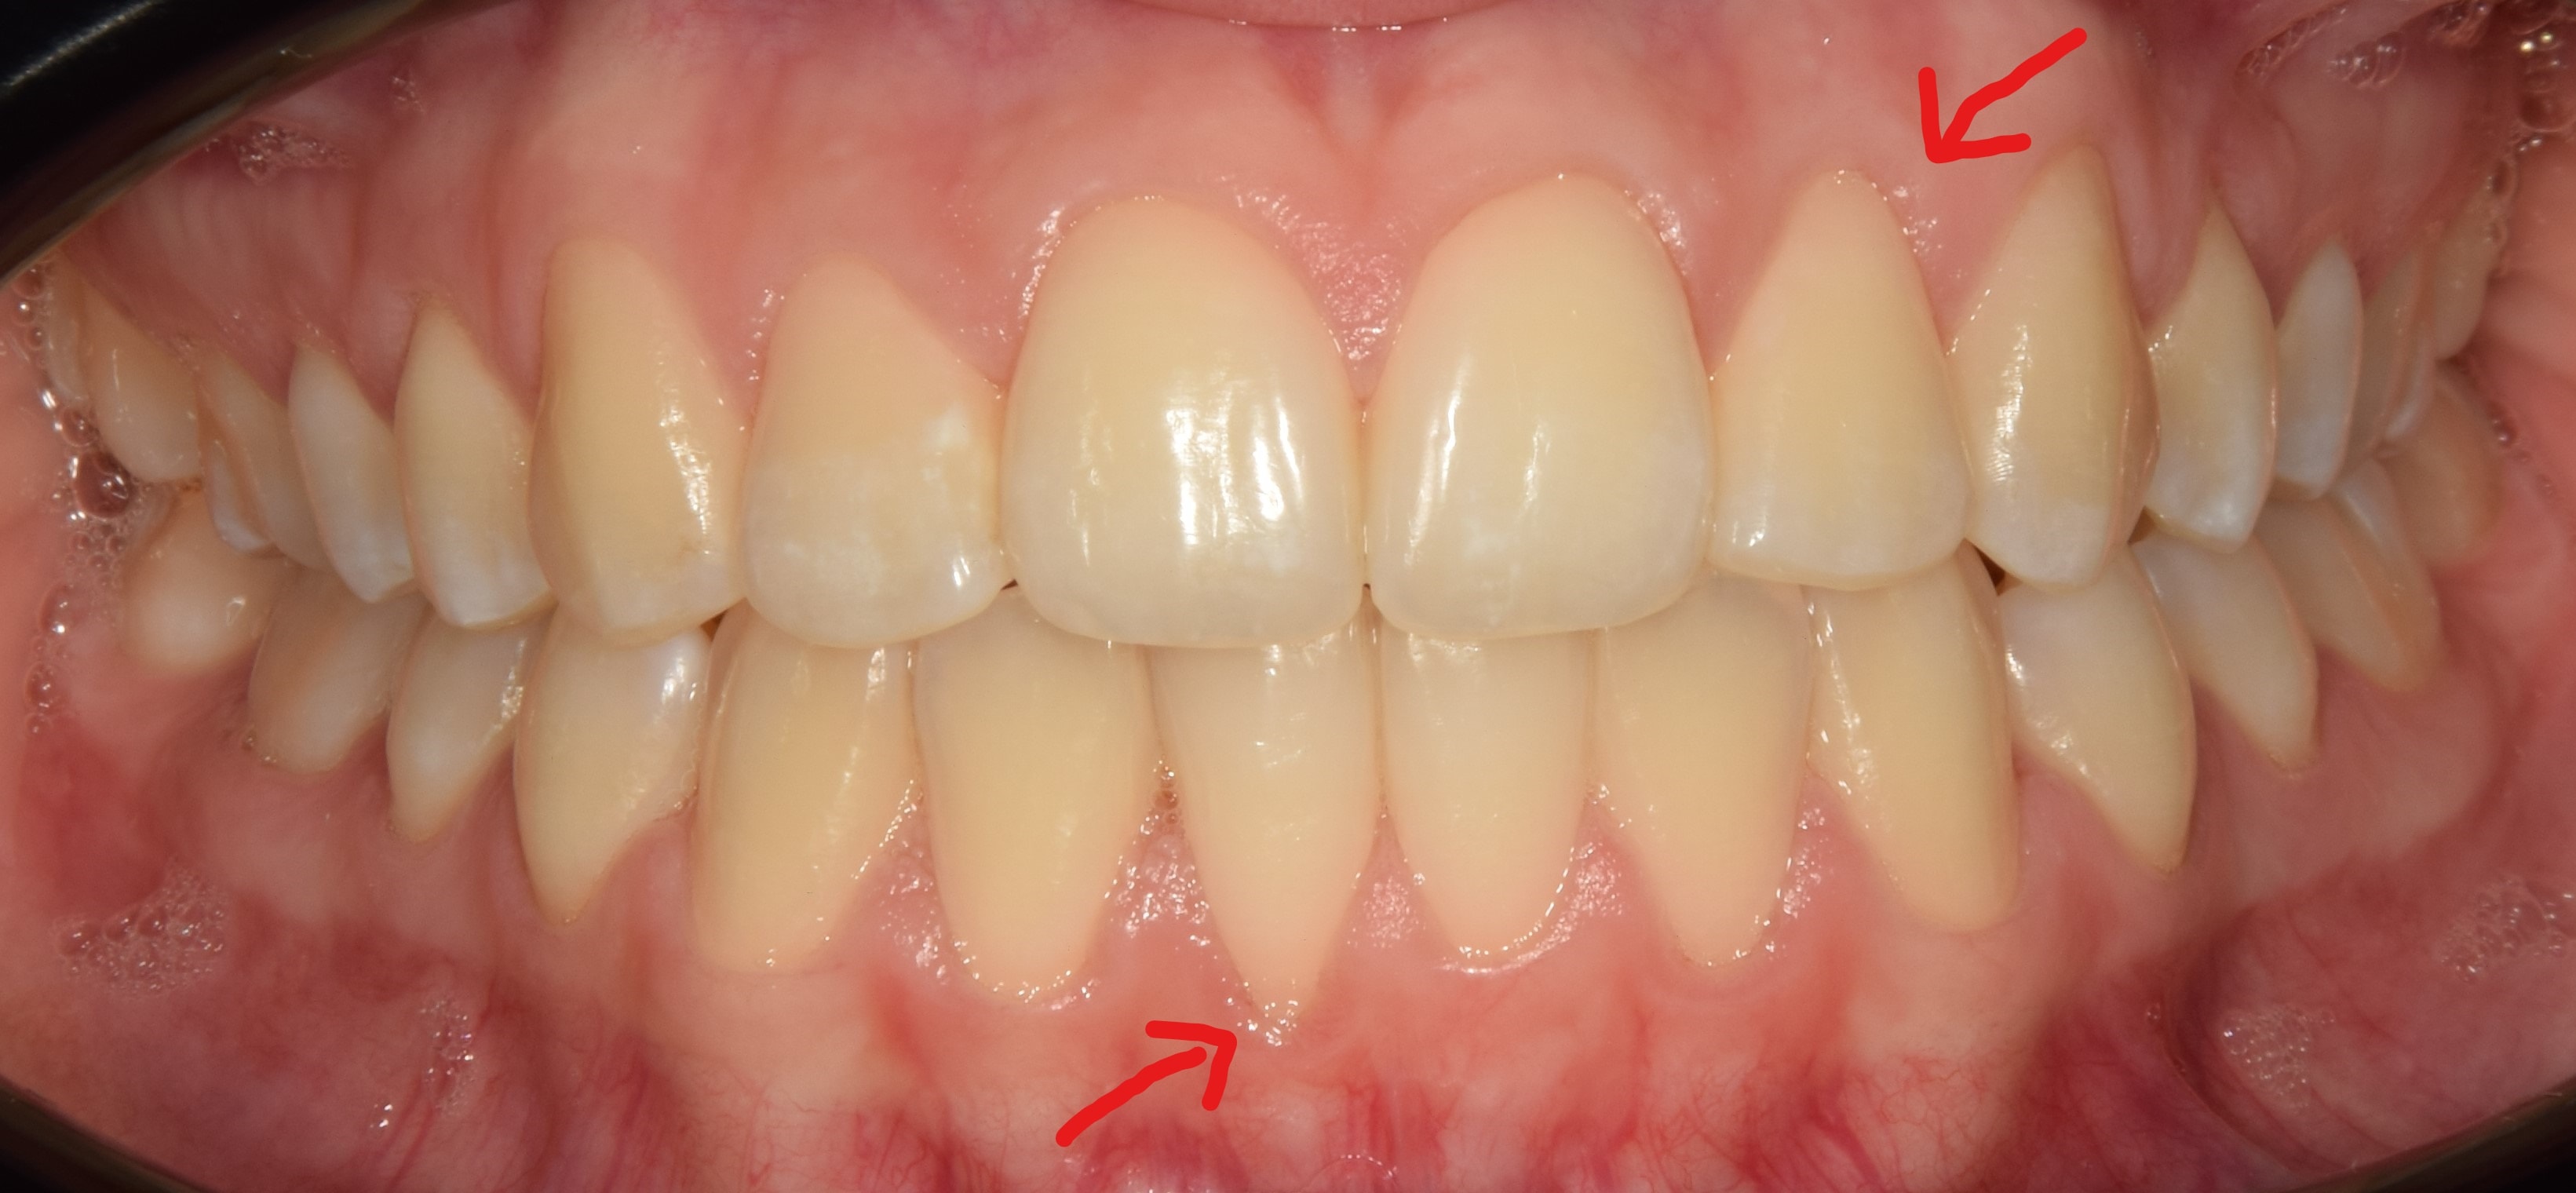

Diasthema medianum

Gyakori fogszabályozási probléma a két felső nagymetsző között jelentkező rés. Ellátását számos faktor befolyásolja. A vegyesfogazatban gyakori, legtöbbször normális jelenség, ami később spontán záródhat, ezért túlságosan korai ellátását semmi sem indokolja. Diasthemat eredményezhet például kifejezett ajakfék, számfeletti fog, kismetsző csírahiány.

Az ajakfék nem más, mint az ajkak mozgását szabályozó, korlátozó nyálkahártya tömörülés, mely az alsó és felső első metszők fölött-között helyezkedik el. A túlságosan kifejezett ajakfék beszédproblémát, ínyvisszahúzódást, vagy akár rést is okozhat a metszőfogak között. A köteges, kifejezett ajakféket egy kis szájsebészeti beavatkozás során korrigálni lehet, legkíméletesebben lézerrel.